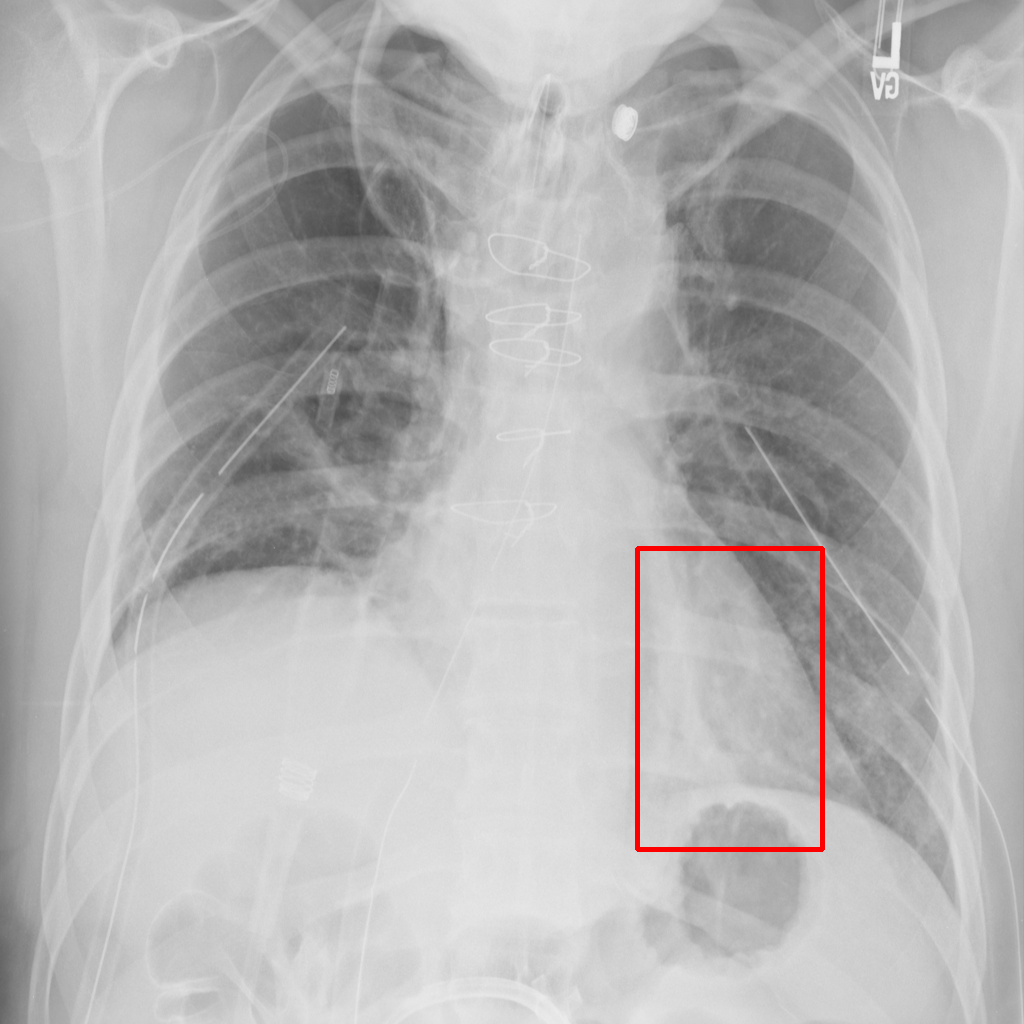

Object Rotation

X-ray GMAIMMbench Disease Diagnosis

Object Rotation - L0 (Original)

L0

L0 (Original)

Question

Given the boxed region in the X-ray image, which abnormality is the image most indicative of?

A pneumothorax B pulmonary fibrosis C bone fracture D pleural effusion

Ground Truth: A. pneumothorax